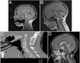

Craniovertebral junction fusion deformity

Fourth ventricle outlet obstruction